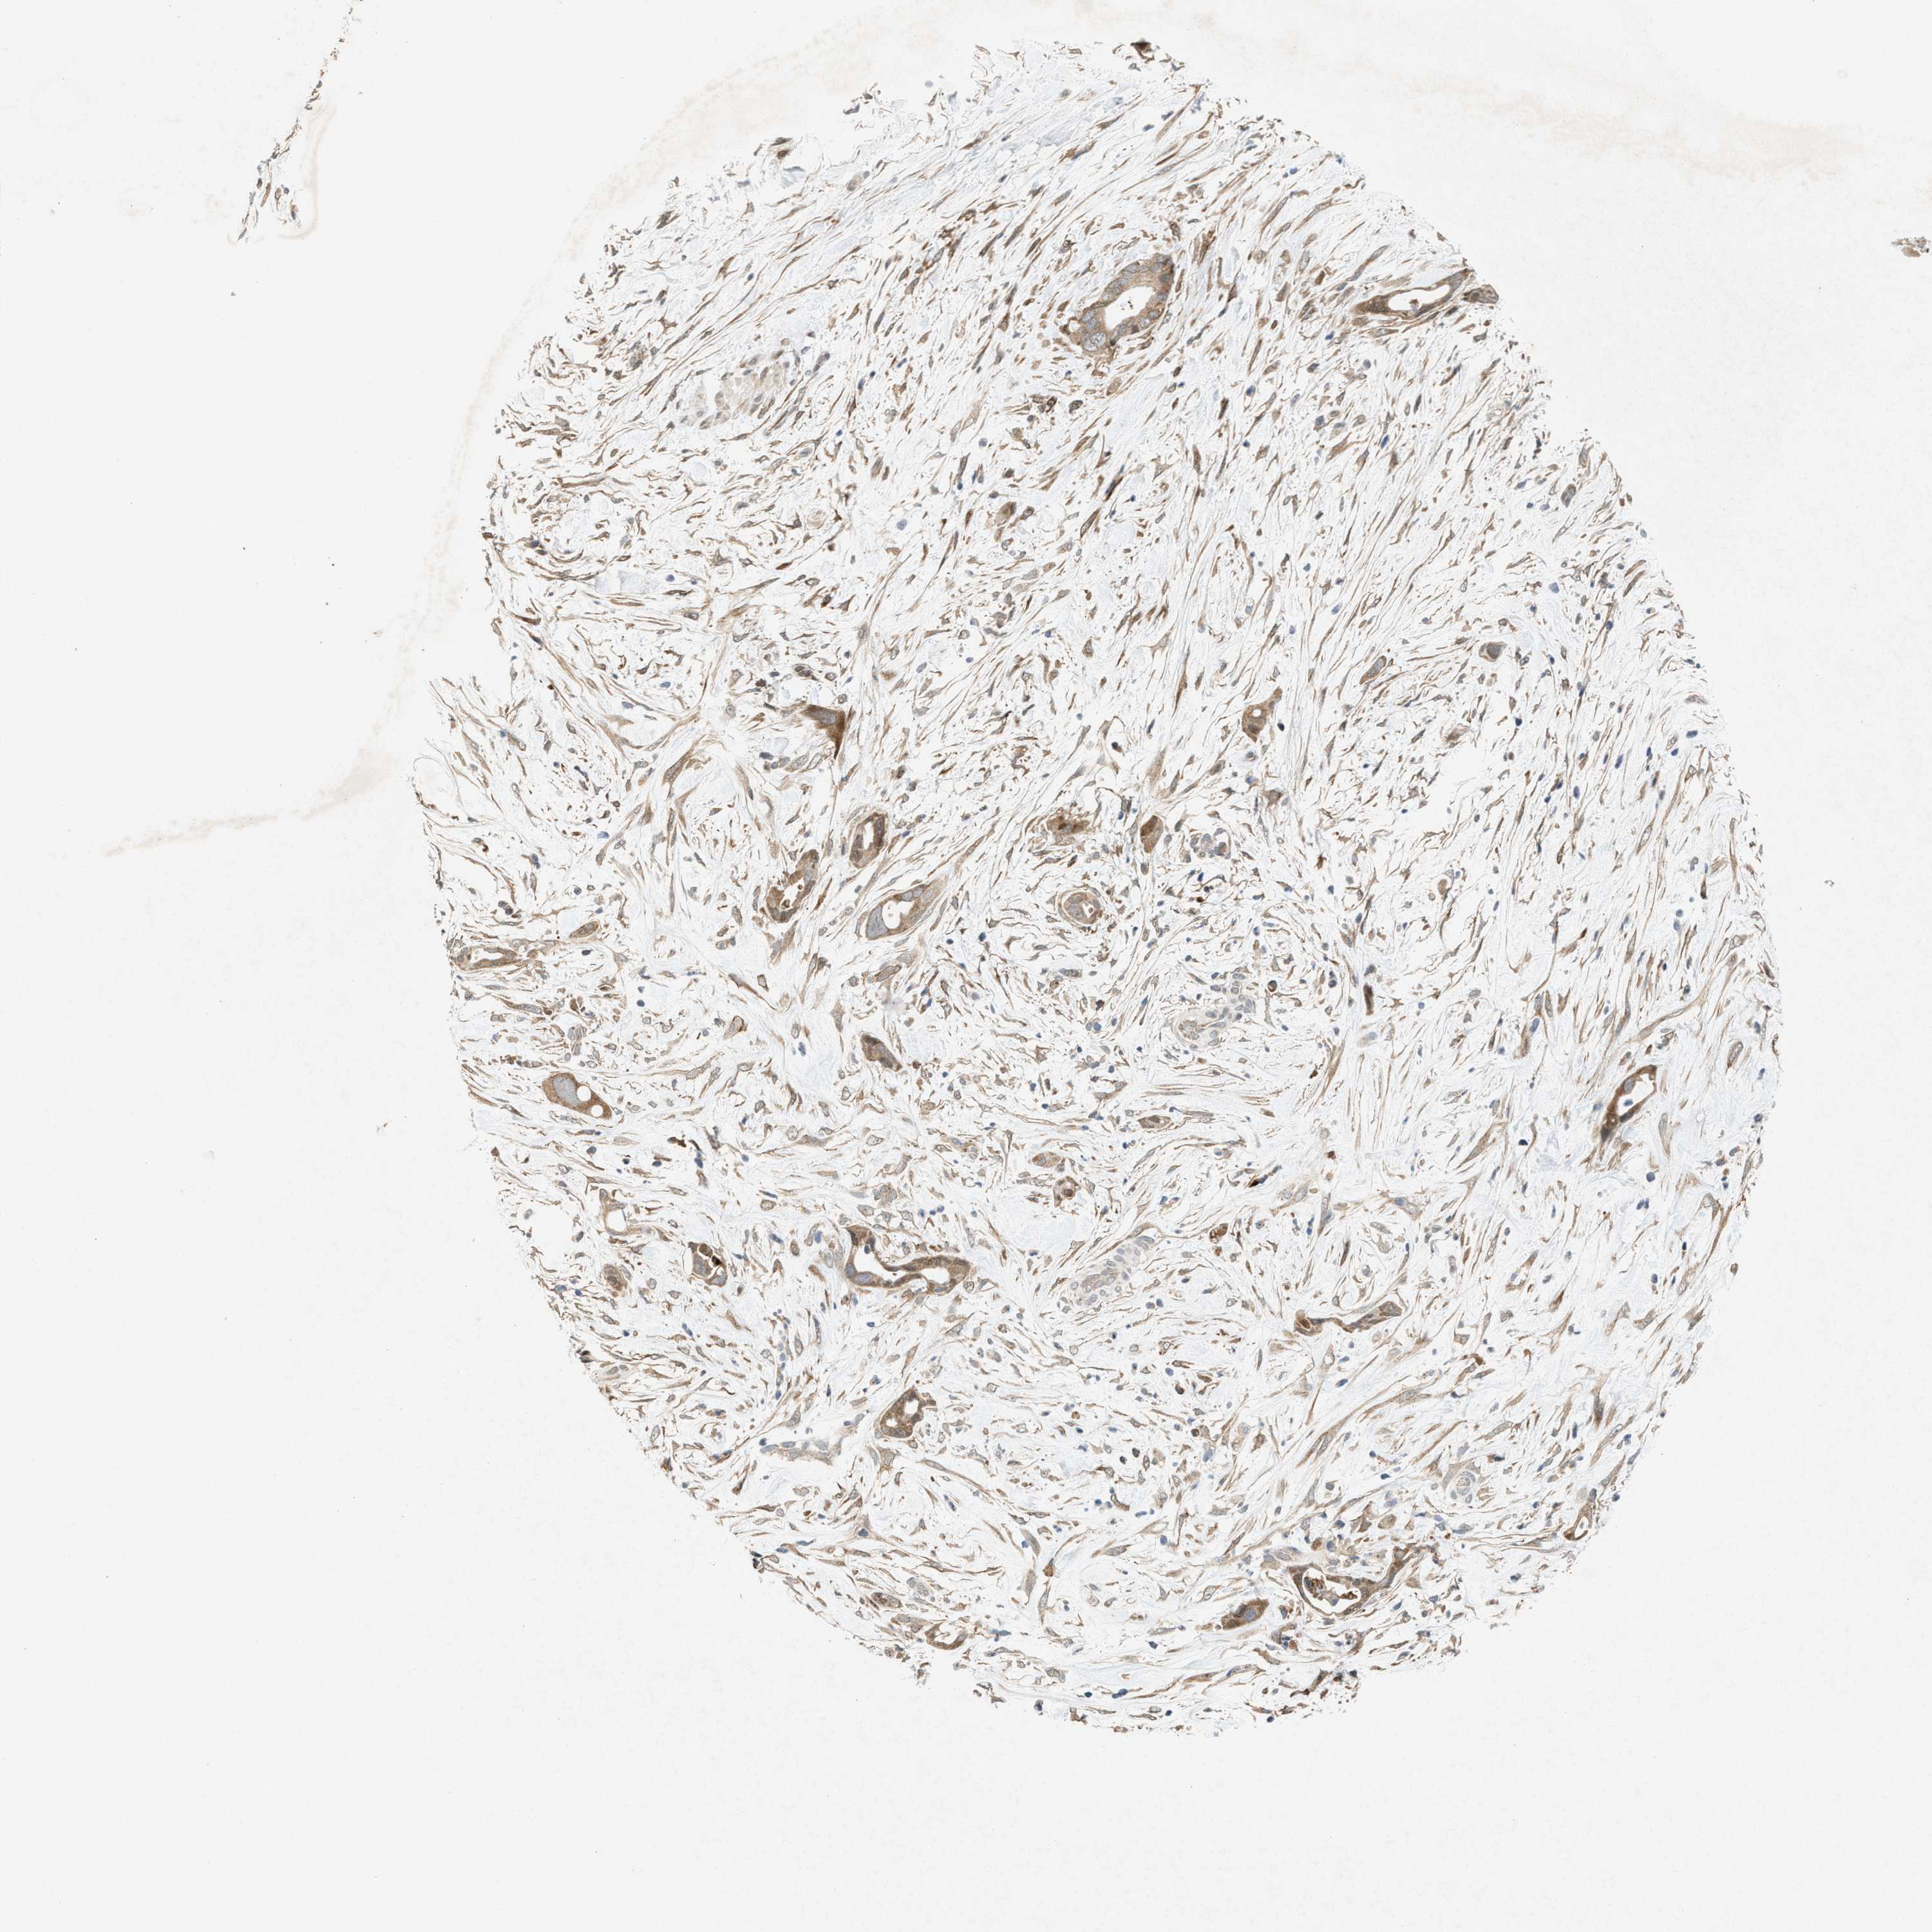

PANCREATIC CANCER - Protein expressioni

A mouse-over function shows sample information and annotation data. Click on an image to view it in a full screen mode. Samples can be filtered based on level of antibody staining by selecting one or several of the following categories: high, medium, low and not detected. The assay and annotation is described here.

Note that samples used for immunohistochemistry by the Human Protein Atlas do not correspond to samples in the TCGA dataset.

Antibody stainingi

Antibody staining in the annotated cell types in the current human tissue is reported as not detected, low, medium, or high, based on conventional immunohistochemistry profiling in selected tissues. This score is based on the combination of the staining intensity and fraction of stained cells.

Each image is clickable and will lead to virtual microscopy that enables deeper exploration of all samples and also displays staining intensity scores, fraction scores and subcellular localization as well as patient and tissue information for each sample.

Antibody HPA022274

Staining

High

Medium

Low

Not detected

Intensity

Strong

Moderate

Weak

Negative

Quantity

>75%

75%-25%

<25%

None

Location

Nuclear

Cytoplasmic/membranous

Cytoplasmic/membranous,nuclear

Adenocarcinoma, NOS